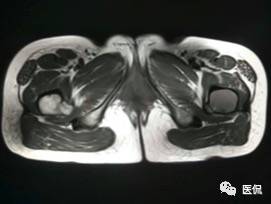

影像资料:

(3)MRI ABC的特征为鼓囊状的膨胀性破坏,呈单囊或由低信号的间隔分隔成大小不等的多囊。因血细胞和血浆的分离和沉淀,囊内可见液-液平面。在T2WI上,液面上层为高信号,下层为低信号;T1WI上则相反,上层为低信号,下层为偏高信号。液-液平面是ABC较特征的征象。增强检查低信号的纤维间隔呈环形强化。继发性动脉瘤样骨囊肿可在其原发病灶内有液-液平。